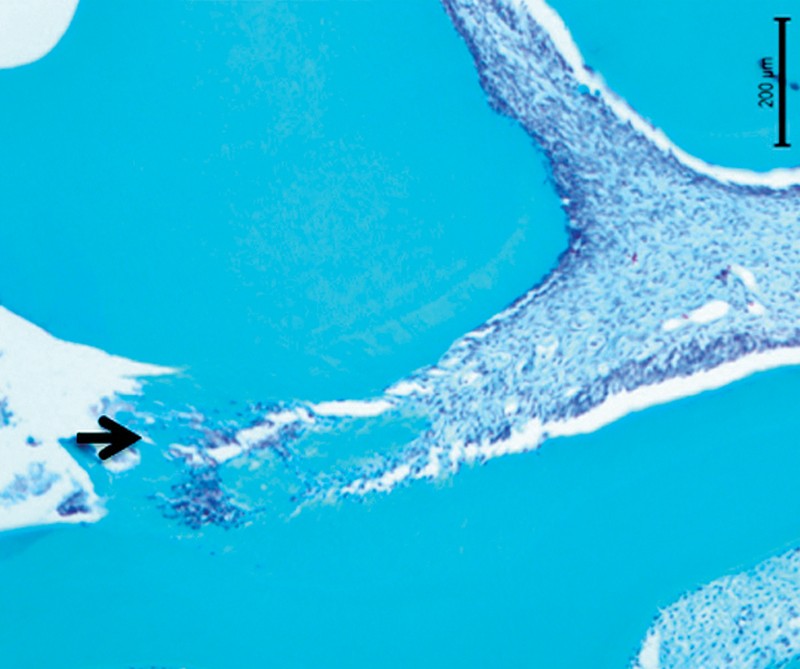

Il est connu depuis longtemps, qu’une pulpe exposée est capable de conserver sa vitalité dès lors que les conditions biologiques et cliniques sont réunies pour qu’un pont dentinaire se forme en fermant la brèche dentinaire présente (1). Le tissu pulpaire ainsi isolé recouvre alors son état de santé et ses fonctions (fig. 1).